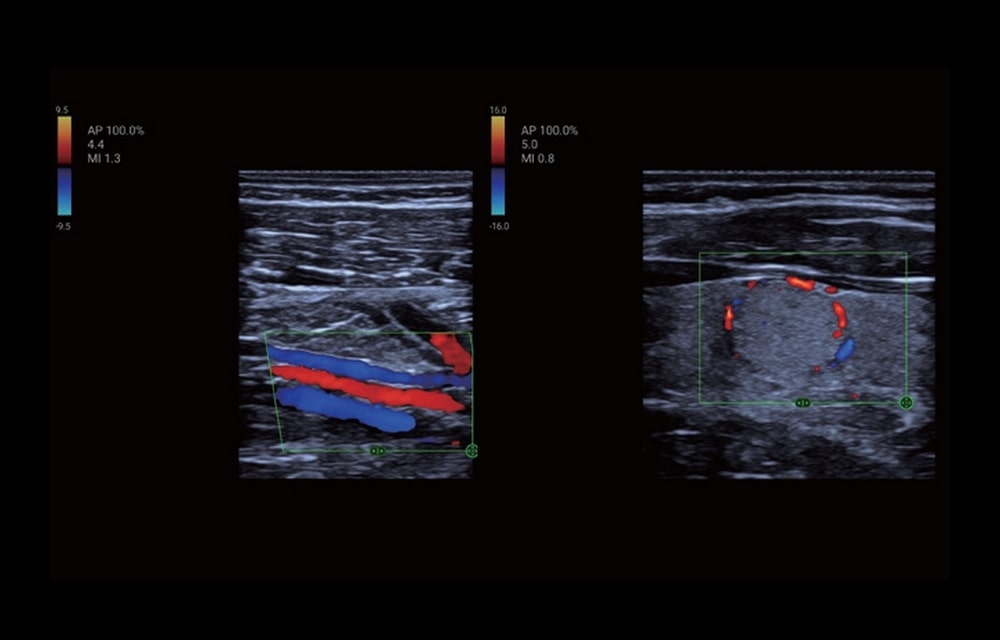

L’ecografo palmare TE Air, rappresenta oggi il Top tra gli ecografi portatili. Il trasduttore collegato ad uno smartphone o ad un tablet in modalità Wifi, garantisce prestazioni full body di qualità superiore alla media degli ecografi ultraportatili. Consente l’uso, in emergenza, di applicazioni diverse.

TE Air grazie alle sue dimensioni ed al peso ridotto è perfetto per uso mobile ed a domicilio del paziente. L’ecografo palmare è molto semplice nel suo utilizzo e pronto all’uso in pochi secondi. La durata della batteria interna garantisce un’autonomia di lavoro superiore all’ora e mezza ed il tempo di ricarica è di soli trentacinque minuti. Facile da pulire, con superficie resistente ai disinfettanti per un impiego igienico. TE Air e5M è in grado di gestire la scansione dell’intero corpo e di adattarsi a vari scenari clinici. Il suo design wireless consente esami ecografici di alta qualità in qualsiasi momento e ovunque. Oltre alla sua versatilità, TE Air e5M offre anche una gamma di funzioni intelligenti e strumenti didattici per aumentare la sicurezza e l’efficienza.